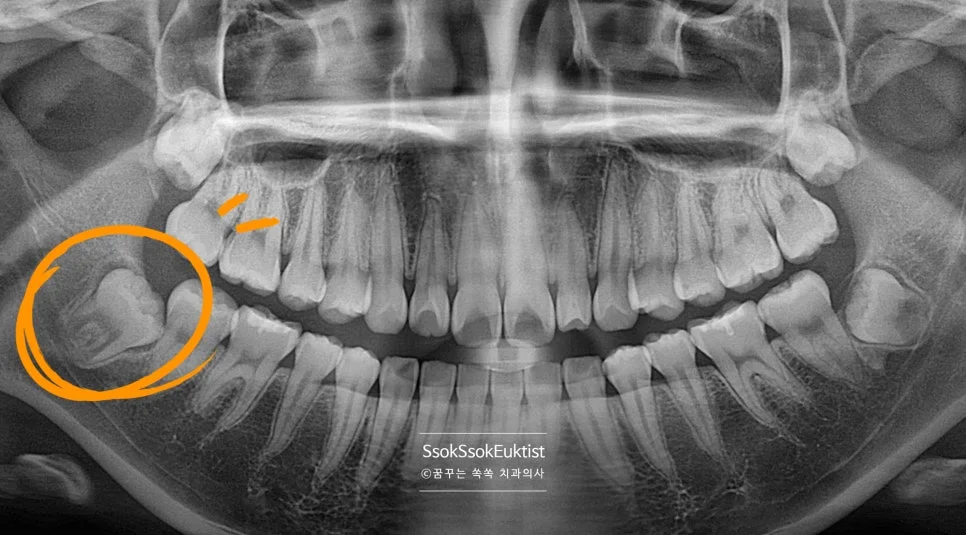

어려운 난이도 — 완전히 누워 있는 수평 매복 사랑니

X-ray 사진을 보면 사랑니가 완전히 누워 있어 사랑니를 빼기 위해서는 깊숙한 곳까지 도달하여 치아를 분리해야 할 것 같은데요~^^

CBCT 3차원 영상 — 서로 다른 방향으로 휘어진 복잡한 뿌리

3차원 사진을 통해 보면 뿌리가 서로 다른 방향으로 휘어 있어 뼈를 잡고 있는 모습인데요^^ 이런 뿌리의 사랑니의 경우 한꺼번에 나오지 않으므로 머리를 분리하는 것 외에 뿌리도 분리하여 사랑니를 제거해야 합니다.

그렇기에 매우 어려운 발치 난도이며, 이러한 어려운 발치를 해낸다면 사랑니 발치를 잘하는 치과로 볼 수 있겠죠^^